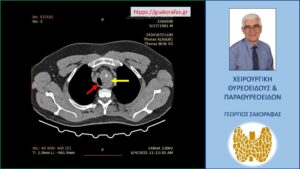

Αξονική τομογραφία – εγκάρσια διατομή σε ακόμη χαμηλότερο επίπεδο. Ο διογκωμένος αριστερός λοβός (κίτρινο βέλος) που απωθεί την τραχεία (κόκκινο βέλος) προς τα δεξιά.

Αξονική τομογραφία – εγκάρσια διατομή σε ακόμη πιο χαμηλό επίπεδο. Ο διογκωμένος αριστερός λοβός (κίτρινο βέλος) που απωθεί την τραχεία (κόκκινο βέλος) προς τα δεξιά.